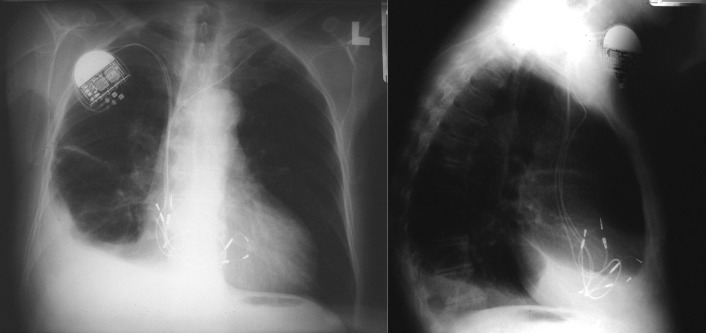

Chest radiography has a standard role in the identification of several potential complications such as pneumothorax, hemothorax, and several forms of malposition after insertion of pacemakers, implantable cardioverter defibrillators (ICDs), and cardiac resynchronization therapy devices.

Pacemaker leads are apparent, and ICDs are more obvious because of their larger coils. Coronary sinus leads for cardiac resynchronization therapy are finer leads.

Endocardial Pacer Leads

The position and integrity of endocardial pacer leads should be verified, especially when pacemaker dysfunction is clinically suspected ( Graphics 23-1 to 23-4 ; Figs. 23-1 to 23-15 ).The most common cause of pacemaker dysfunction that is apparent on the chest radiography is distal lead displacement/misplacement.

With a right atrial lead , the tip should be in the right atrial appendage.

With a right ventricular lead , the tip should lie anteriorly at the apex of the heart.